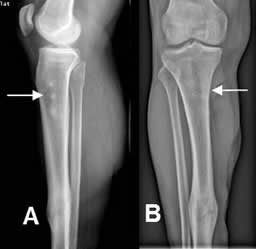

Fig 120. Zona debilitada.

A: Rx lateral y B: Rx AP. Callo óseo en la diáfisis tibial. En la tibia proximal hay una zona debilitada, por el retiro de los tornillos que fijaban un clavo de Kuntcher.